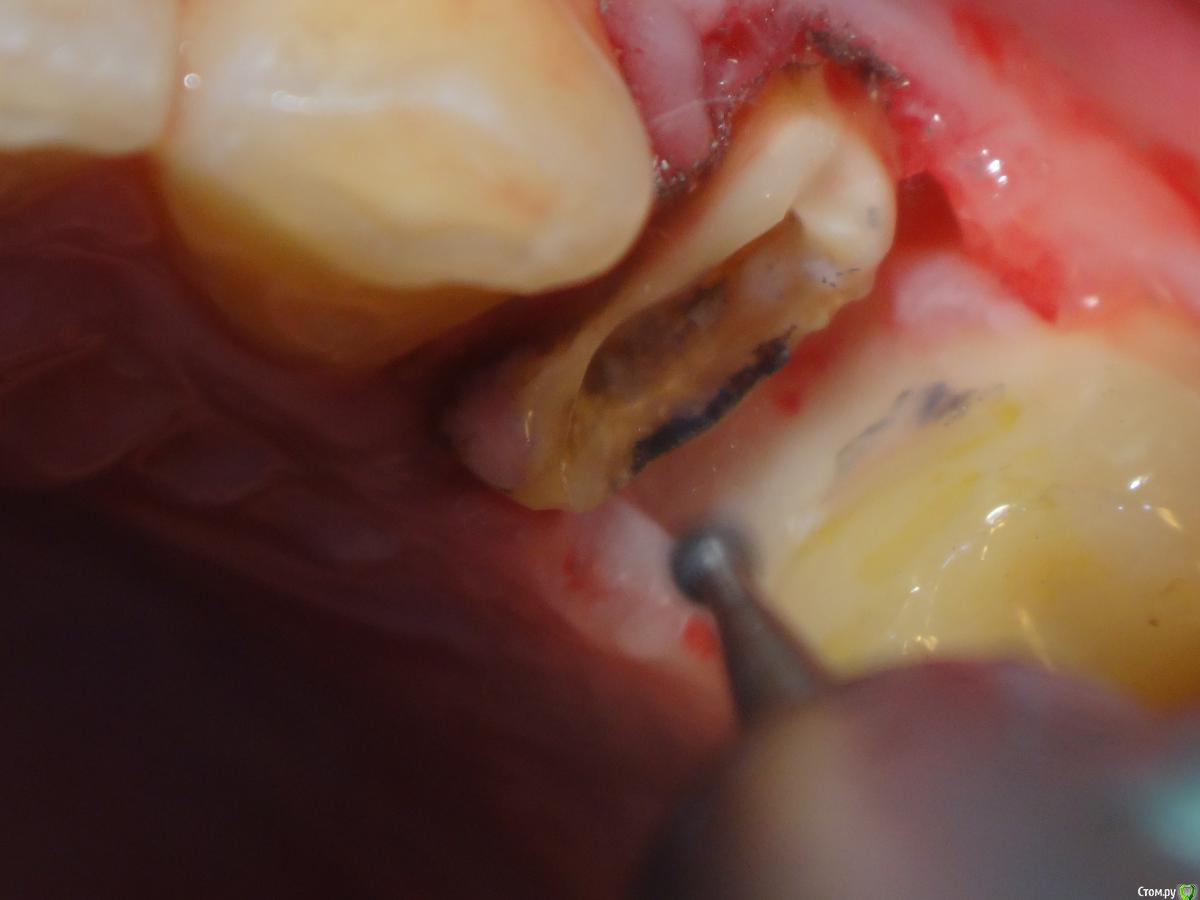

Slaggy Опубликовано 21 января, 2015 Поделиться Опубликовано 21 января, 2015 (изменено) Как раз давеча разобрал одного марджтнэлеватораПациент обратился с целью переделать коронку.Стояла литая вкладка + коронка. Коронка пришла в негодность.Пошлифовал края, переделал коронку - дважды за месяц проблемы с сосочком.Срезал коронку.Удалил литую вкладку и увидел черный край )))) Далее пришлось убрать грануляции, пройтись лазером, сгладить косточку, подшить повязку, отправить на пару месяцев с провизорной коронкой. И не виноватая я, но при этом моя работа на помойку. Вот такой вот он - марджин элевэйшн. Изменено 21 января, 2015 пользователем Slaggy Ссылка на комментарий

Hans85 Опубликовано 21 января, 2015 Автор Поделиться Опубликовано 21 января, 2015 Как раз давеча разобрал одного марджтнэлеватораПациент обратился с целью переделать коронку.Стояла литая вкладка + коронка. Коронка пришла в негодность.Пошлифовал края, переделал коронку - дважды за месяц проблемы с сосочком.Срезал коронку.Удалил литую вкладку и увидел черный край )))) DSC01785.JPGДалее пришлось убрать грануляции, пройтись лазером, сгладить косточку, подшить повязку, отправить на пару месяцев с провизорной коронкой. И не виноватая я, но при этом моя работа на помойку. Вот такой вот он - марджин элевэйшн.а рентгена нет,и я не совсем понял то есть вы сделали коронку на вкладке??,если вы делали то вкладку как фиксировали ,на какой материал,с коффером?? Ссылка на комментарий